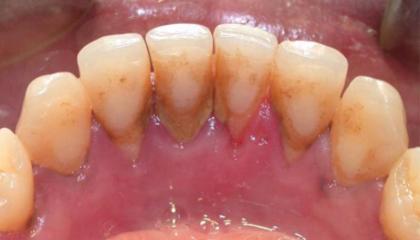

• Tartar removal1

Tartar Removal BEFORE